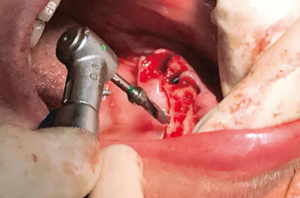

Per posizionare la dima chirurgica per la tecnica All-on-Four realizzo in zona mediana un foro con un diametro di 1,2 mm e una lunghezza di 10 mm (Figg. 14, 15). Le tacche verticali presenti sulla dima chirurgica All-on-Four, distanziate tra loro 7 mm, aiutano a dare la corretta inclinazione agli impianti distali, che sono i primi ad essere inseriti: posizionando la fresa sulla diagonale tra due tacche consecutive si ottiene un’inclinazione di circa 30°.

- Fig. 14

- Fig. 15

Si preparano quindi prima i due siti distali per gli impianti 3,3 x 12 mm utilizzando le frese Leone con stop integrale passando come ultima fresa quella dedicata per tutta la lunghezza. L’osso, essendo molto denso, ha bloccato l’inserimento degli impianti con il manipolo ad una distanza di circa 4 mm prima di arrivare nella posizione finale.

Ho proceduto quindi manualmente con il cricchetto portando gli impianti in sede (Figg. 16, 17).